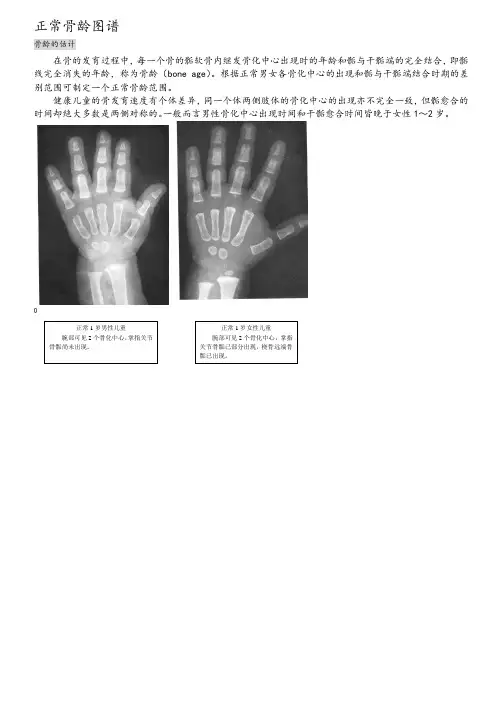

正常骨龄图谱

骨龄的估计

在骨的发育过程中,每一个骨的骺软骨内继发骨化中心出现时的年龄和骺与干骺端的完全结合,即骺线完全消失的年龄,称为骨龄(bone age)。

根据正常男女各骨化中心的出现和骺与干骺端结合时期的差别范围可制定一个正常骨龄范围。

健康儿童的骨发育速度有个体差异,同一个体两侧肢体的骨化中心的出现亦不完全一致,但骺愈合的时间却绝大多数是两侧对称的。

一般而言男性骨化中心出现时间和干骺愈合时间皆晚于女性1~2岁。

正常1岁男性儿童腕部可见2个骨化中心,掌指关节骨骺尚未出现。

正常1岁女性儿童腕部可见2个骨化中心,掌指关节骨骺已部分出现,桡骨远端骨骺已出现。